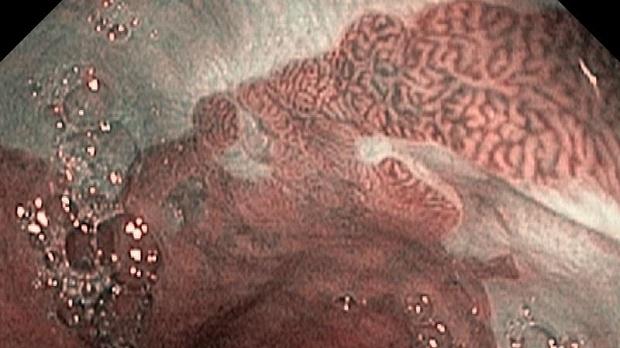

Появление ультратонких гастроскопов с высоким разрешением и технологией NBI (оптического узкоспектрального режима) компания OLYMPUS сделала возможной гастроскопию экспертного уровня под местной анестезией, без наркозных рисков.

Ультратонкие гастроскопы GIF-XP170N и GIF-XP190N с параметром оптики Close Focus, который позволяет приближаться к слизистой на минимальную глубину резкости до 2 мм, обеспечивают качество изображения, сопоставимое с аппаратами экспертного класса.

В Центре Экспертной Эндоскопии, г. Симферополь с июня 2018 с помощью этих эндоскопов выполнено более 1000 эндоскопических исследований, с полным соблюдением критериев качества ESGE. Среднее время исследования составило 14мин. 51с. Все исследования выполнялись с предварительной подготовкой желудка, применением водяной помпы и СО2-инсуффлятора, фото- и видеодокументацией.

Использование в ежедневной рутинной практике современных ультратонких эндоскопов высокого разрешения с технологией оптического узкоспектрального режима (NBI® OLYMPUS™) под местной анестезией позволило полностью обеспечить соответствие критериям качества выполнения эндоскопических исследований, определенным ESGE. Данный метод комфортен для пациента под местной анестезией, безопасен, является простой и удобной альтернативой ЭГДС под седацией, что особенно важно в амбулаторных условиях.